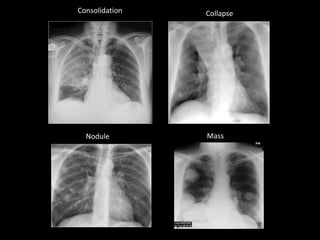

Consolidation Collapse

Nodule Mass